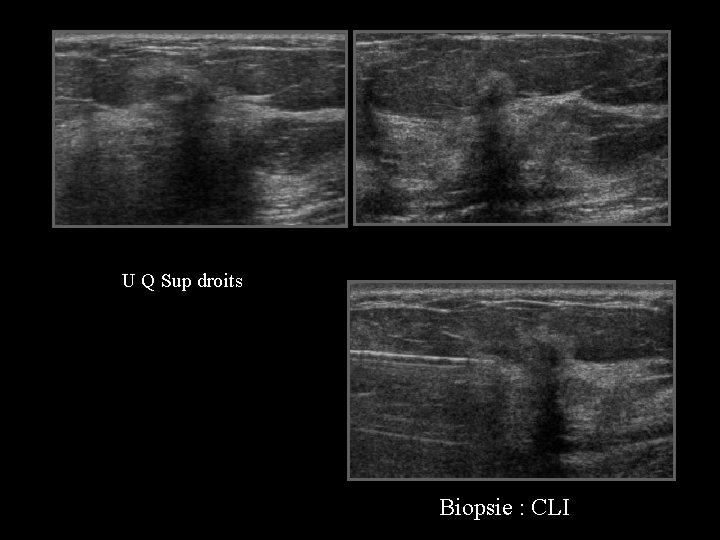

D face ext 46 ans, placard QSE droit de 4 cm palpé par la gynécologue

U Q Sup droits Biopsie : CLI